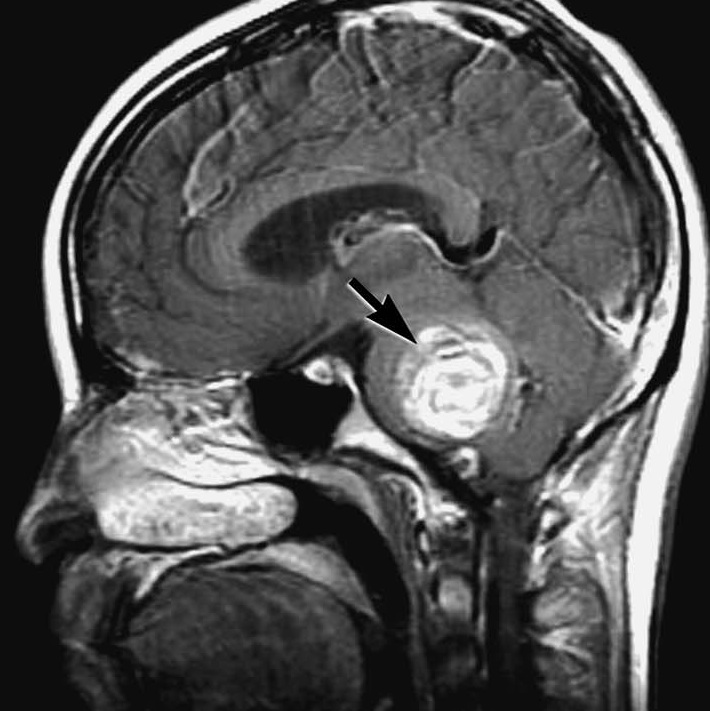

由于计算机断层扫描(CT)和磁共振成像(MRI)的使用增加,近年来诊断出更多的CHs。非对比CT扫描显示三脑室内有不均一的高密度出血肿块压迫下丘脑,没有明...

我们报告一例视交叉性黄斑变性,具有经典的临床和影像学表现。颅咽管瘤被认为是较有可能的,部分血栓形成的动脉瘤,海绵状血管瘤,出血性神经胶质...